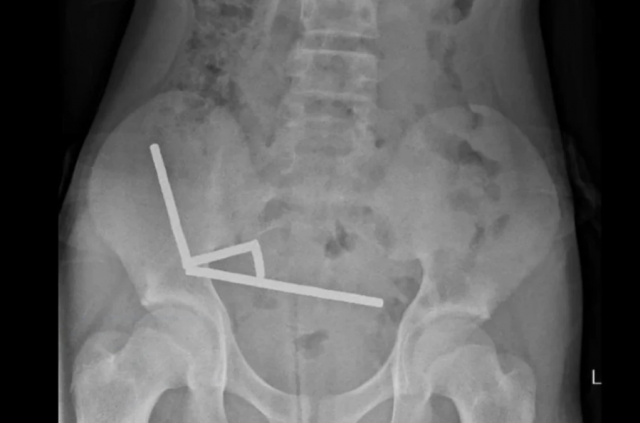

医生在影像检查中发现,大量磁铁分布在肠道不同部位,部分已经相互吸附穿透肠壁,形成闭环。